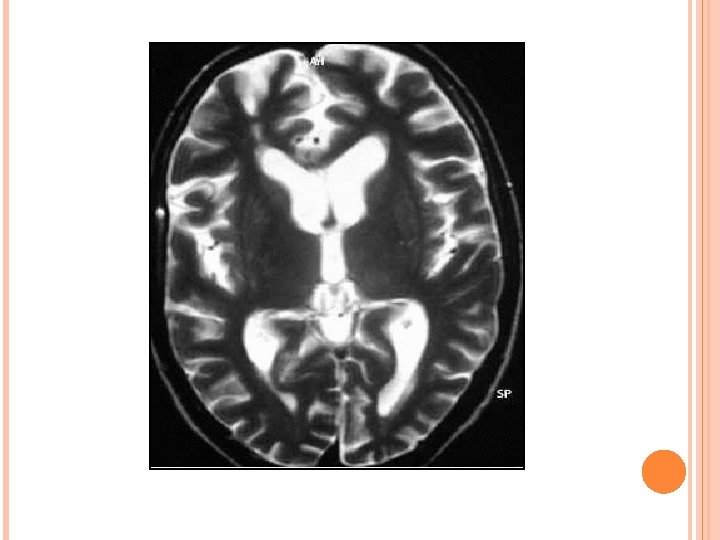

PROGRESSIVE MULTIFOCAL LEUKOENCEPHALOPATHY • ETIOLOGY- JC virus. Ubiquitous virus. Immunodificiency. Most common predisposing condition = HIV (80%). • Three phases of devlopment. Virus exclusively affect the oligodendrocytes. Multifocal demyelination. Predominantly affect parietal & occipital lobes. posterior fossa white matter and basal ganglia involvement is also present. CNS manifestation are c. PML , i. PML, JC encephalitis/meningitis.

IMAGING: Multifocal WM lesions but may be unifocal. Bilaterally assymetric. Involve subcortical U fibers. Spare cortex. No mass effect/enhancement (except i. PML) On DWI, varies according to disease stage. MRS- Decrease NAA, increased choline and lipid lactate peak. p. MRI – shows reduced r. CBV. D/D- HIVE, PML-IRIS, CMV.